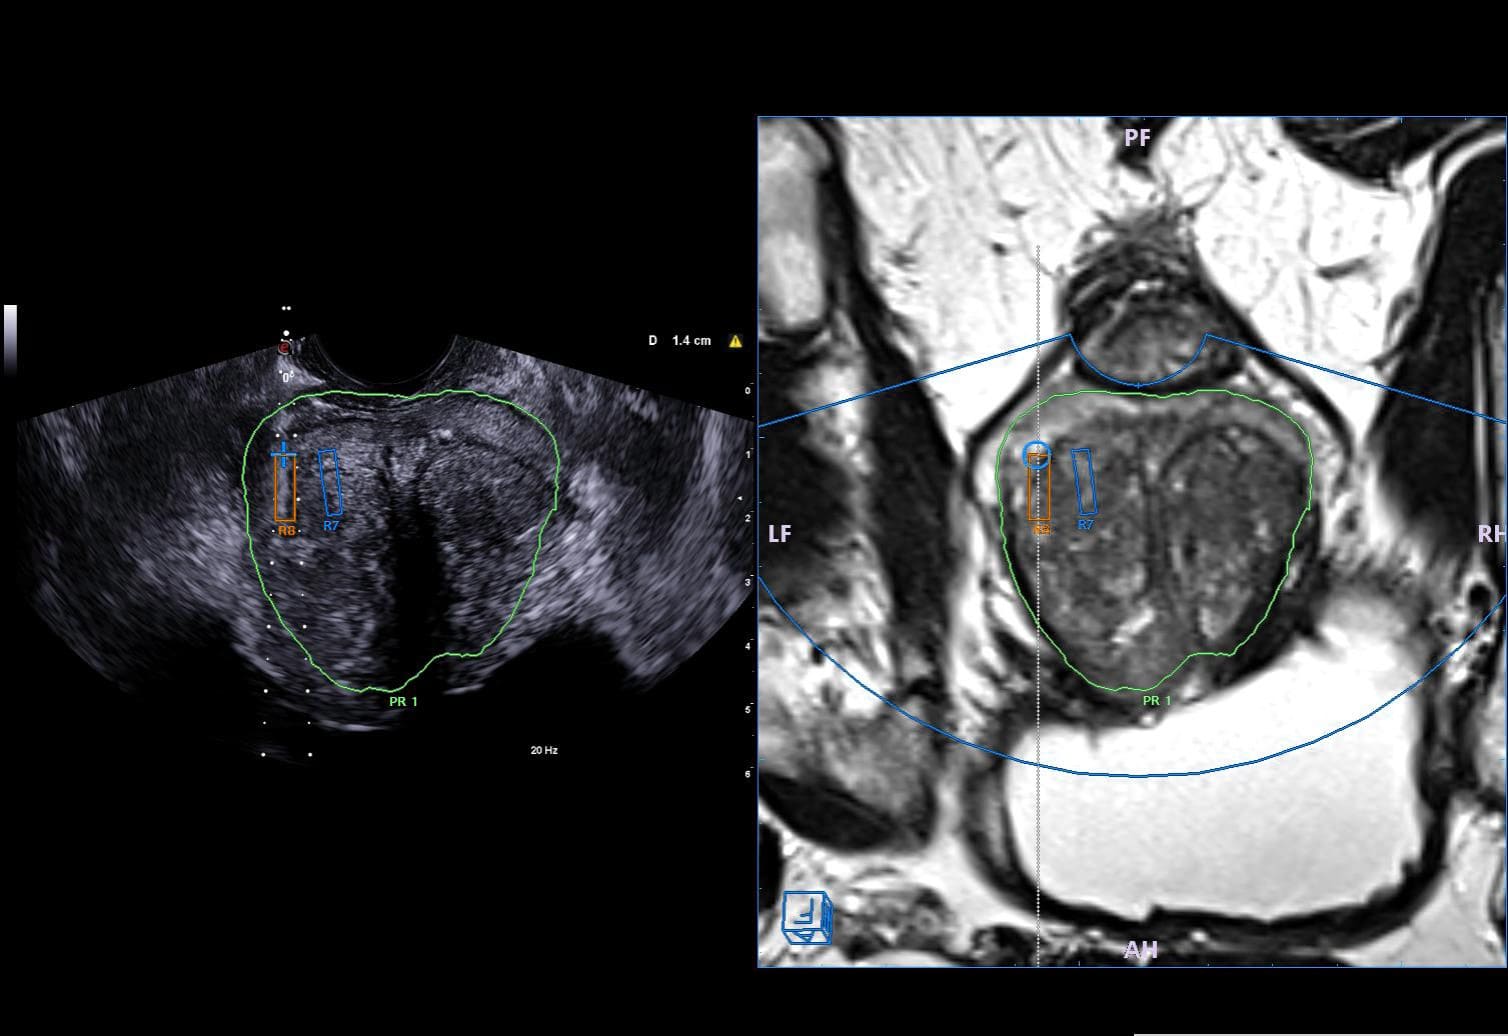

- Fusion imaging funkcijos pagalba sinchronizuojami dviejų diagnostinių įrankių (MRT, KT, PET, radiografijos, mamografijos) 2D arba 3D vaizdai